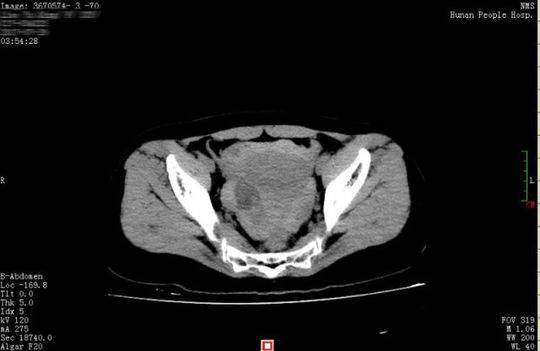

26 歲的小晴和28 歲的小東是一對新婚夫婦,因工作的緣故兩地分居。8 月16 日,近半年未見丈夫的小晴回到長沙。晚上,小別勝新婚的兩人免不了親熱一番。誰知激情過后,小晴出現下腹部疼痛,而且越痛越厲害,只得來到湖南省人民醫院天興閣院區急診科就診。尿妊娩檢查結果為陰性,而腹部CT 提示盆腔、腹腔有大量積血、積液,隨即轉入婦科。黃薇副主任醫師接診后發現,小晴面色蒼白,渾身大汗淋漓,脈搏為102 次/ 分,呼吸22 次/ 分,血壓89/54mmgH, 血紅蛋白為79g/l, 已達到失血性休克的標準。

黃薇立即為小晴進行診斷性腹腔鏡手術,術中發現腹腔內積血約1500ml,接近她全身總血量的40%," 再晚一點來,就會危及生命了"。醫生還發現,在她右側卵巢有一個直徑3cm 左右的黃體囊腫表面有破口,破口有血塊附著,還有活動性出血。黃薇立即為她施行黃體囊腫剝除和創面縫合止血手術,恢復了卵巢的正常形態。